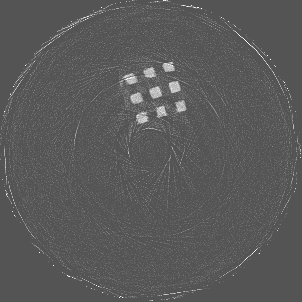

Using the Ti scaffold sample, a post reconstruction analysis between Si detector (Medipix3.1) operating in Single Pixel Mode (SPM) and CdTe detector (Medipix3RX) operating in CSM was carried out. Figure 6a shows a reconstruction for energy range 30 to 50 keV obtained using Si detector with a detector element size 55 μ𝜇\mum in SPM. Despite good spatial resolution, artefacts are still prominent. The reconstruction using CdTe detector with a detector element size of 110 μ𝜇\mum in CSM (figure 6b) shows reduced artefacts comparatively. To obtain the narrow energy range of 35 to 55 keV, the raw counts at 35 to 80 keV and 55 to 80 keV were subtracted.

Refer to caption

(a) 30 to 50 keV using Si

(b) 35 to 55 keV using CdTe

Figure 6: Ti scaffold reconstruction using Si Medipix3.1 and CdTe Medipix3RX.